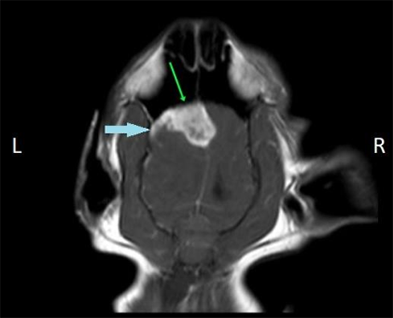

МРТ при неврологических симптомах у кота

Пациент: Барсик, кот, 4 года

Жалобы: Односторонняя слабость, нарушение координации, эпизодическая атаксия. После одного из приступов — временная потеря ориентации.

Диагноз: МРТ головного мозга выявило фокальное воспалительное изменение в области мозжечка — картина, соответствующая очаговому менингоэнцефалиту. Без признаков новообразования или гидроцефалии.

Что дало МРТ: МРТ обеспечил высокую детализацию мягких тканей мозга, что позволило точно локализовать патологический очаг и начать иммуносупрессивную терапию до прогрессирования симптомов.

Результат: Уже через 10 дней — значительное улучшение координации. Через 6 недель — полное восстановление двигательной функции.